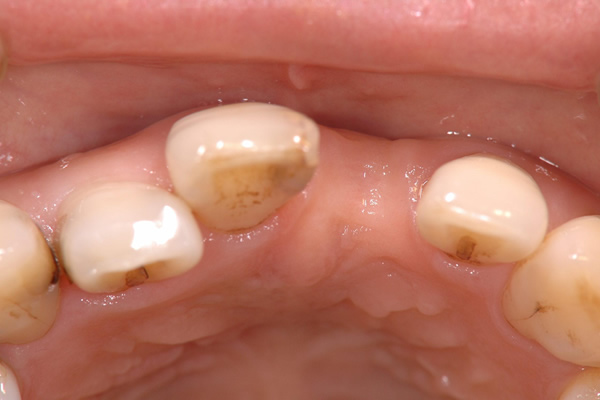

歯科治療では、インプラント治療に限らず見えない部位を診断するために上図のようなレントゲン写真を撮影する必要があります。

当院では、確実な現像・定着・水洗・乾燥・保存処置を行うことで考えられる最高のレントゲン写真の質を確保しています。

しかしながら、立体的な被写体(歯、顎骨など)に対してフィルムやパソコン上に写っているものはあくまで平面的な(2次元的な)像で実物とは異なります。

私たち歯科医師は知識と経験から頭の中で得られた画像を立体的にふくらませているというのが一般的なのです。

そこには像のゆがみや、実際の治療の段階で想定外の口腔内の状態であることが多くあるのも事実です。

CT 撮影をすることによってインプラントを埋入する骨の状態(厚み、高さ、欠損状態、密度)や神経・血管の位置をあらかじめ正確に把握でき、安全に速いインプラント治療が可能となりました。